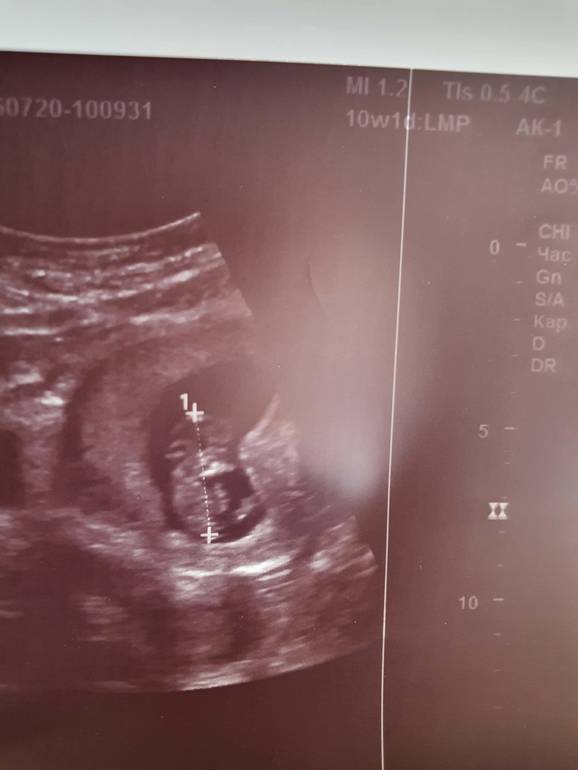

Пол малышаУзнала про такой метод и стало интересно. Мне кажется, что у меня девочки, такое чувство. А что можно сказать по узи? УЗИ вагинальное.

Я могу предположить девочку, по картинке ниже) В методе я не очень разобралась.

По этому методы в 6-8 недель нужно узи посмотреть. Сейчас у тебя уже больше срок